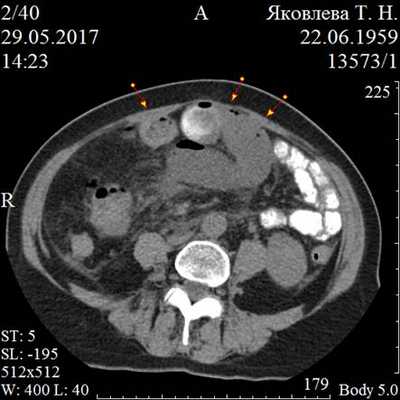

В большей степени выявленные отклонения, определяющиеся существенным раздуванием петель тонкой кишки, заполненных жидкостным содержимым без пузырьков газа, утолщением стенок и преобразованием структуры кишечной стенки в нескольких областях брюшной полости, концентрацией свободной жидкости более 200 мл, указывают на наличие кишечной непроходимости при СББ и возникновение тяжелейшего осложнения -ранней ОКН (рис. 2). Без сомнений, возникала необходимость экстренно изменить тактику лечения.

Рис. 2. РКТ картина ранней острой спаечной тонкокишечной непроходимости через 10 дней после оперативного вмешательства по поводу гистерэктомии